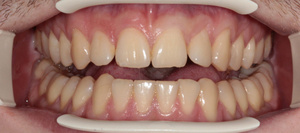

Спасибо всем большое. Дождался заказной вспышки и внутриротовых зеркал с контрастерами.

Все прблемы ушли. Конфигурация техники: Кэнон 550, объектив Кэнон 100/2.8 макро, вспышка Макро

МТ-24ЕХ, зеркала металл YDM.

Ещё. Какие замечания по настройкам?горизонт завален...

мне кажется выглядит не очень и не естественно, а ещё ФШ сюда бы наложить и резкости